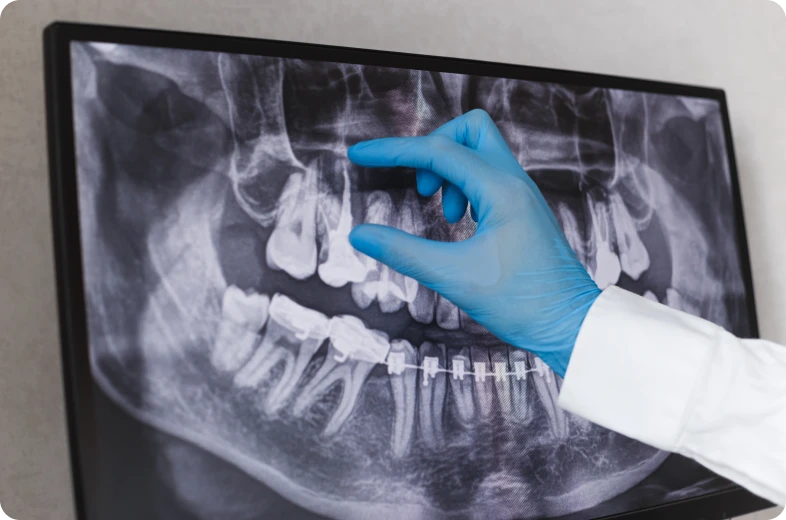

Dans de nombreux cas, l’évolution reste silencieuse pendant une période prolongée. Les résorptions sont donc fréquemment découvertes lors d’examens radiographiques réalisés dans le cadre d’un suivi. Une bonne compréhension de ce phénomène permet d’envisager une prise en charge adaptée.

Le diagnostic repose sur l’association d’un examen clinique et d’examens d’imagerie. L’évaluation clinique permet d’analyser l’état de la dent et sa vitalité, mais elle reste souvent insuffisante à elle seule.

Les radiographies permettent de visualiser les zones de résorption et d’en préciser la localisation. Dans certaines situations, une imagerie tridimensionnelle peut être indiquée afin d’affiner le diagnostic.